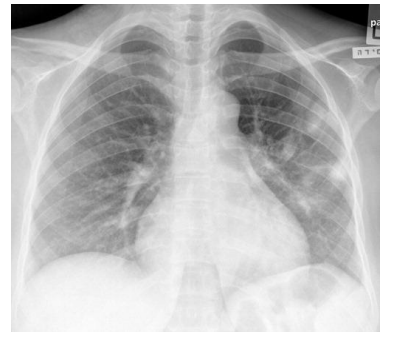

Escolar de 7 anos, acompanhado no ambulatório, foi levado à emergência por dispneia. Mãe relatou que filho estava há

2 dias com mialgia, febre e coriza, evoluindo nas últimas 12 horas com piora da febre e dispneia progressiva. Ao exame,

estava febril (39ºC), taquidispneico, PA no percentil 90 e com SpO2 = 88% em ar ambiente. Realizada radiografia de

tórax (abaixo). O resultado de RT-PCR foi positivo para influenza A e negativo para Covid-19. Os exames laboratoriais

mostraram leucocitose com linfopenia, PCR elevada, e pró-calcitonina baixa.

Diante do caso, qual a principal suspeita diagnóstica e a conduta adequada?